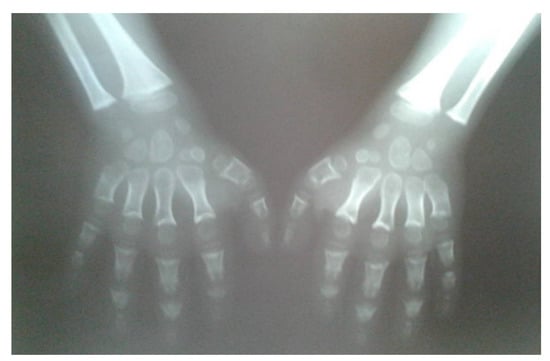

A 15-year-old boy suffering from SWS was born from the third pregnancy of nonconsaguine young and healthy parents as a hypotrophic infant with a perinatal risk factor which included intrauterine growth retardation and asphyxia. Complex phenotypic dysmorphic features were observed at birth. The phenotype of our patient includes multiple facial and skeletal disorders: midface retrusion, prominent forehead, frontal bossing, shallow orbits, downslanted palpebral fissures, narrow nasal bridge, large filtrum, micrognathia, small hands with short metacarpal bones and short distal phalanges of fingers with consequent brachydactyly, knee flexion contracture, pseudoarthrosis, calcaneovalgus deformity, thoracic scoliosis, lumbar hyperlordosis, coxa valga, skeletal dysplasia, pectus carinatum, generalized hypotonia, global developmental delay, cognitive impairment, complete lack of adipose tissue with consequent pseudohypertrophy of muscles, bilateral cataracts and progeroid facial appearance (Figure 1 and Figure 2). As a part of the syndrome, an extremely short stature, body weight of 15 kg and body height of 100 cm were observed.

Figure 1. Radiographs of hands (10 years of age) revealed brachydactyly; wide and shortened phalanges of the fingers, cone-shaped epiphyses of phalanges, short metacarpals.